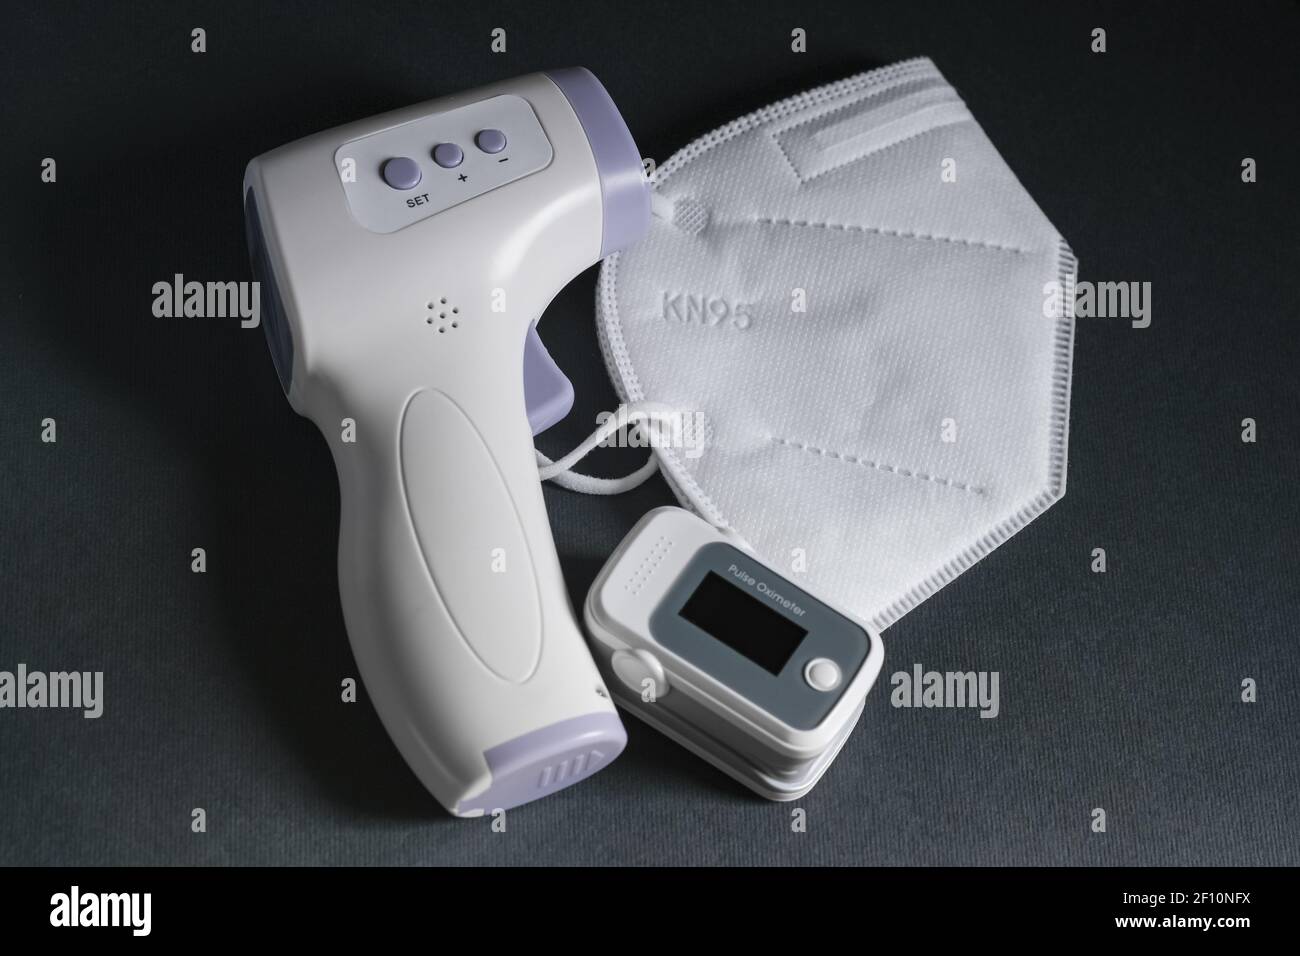

Pulse oximeter,digital fever thermometer and ffp2 protective face mask,covid19 pandemic disease,medical tools home treatment Stock Photohttps://www.alamy.com/image-license-details/?v=1https://www.alamy.com/pulse-oximeterdigital-fever-thermometer-and-ffp2-protective-face-maskcovid19-pandemic-diseasemedical-tools-home-treatment-image413680398.html

Pulse oximeter,digital fever thermometer and ffp2 protective face mask,covid19 pandemic disease,medical tools home treatment Stock Photohttps://www.alamy.com/image-license-details/?v=1https://www.alamy.com/pulse-oximeterdigital-fever-thermometer-and-ffp2-protective-face-maskcovid19-pandemic-diseasemedical-tools-home-treatment-image413680398.htmlRF2F10NFX–Pulse oximeter,digital fever thermometer and ffp2 protective face mask,covid19 pandemic disease,medical tools home treatment